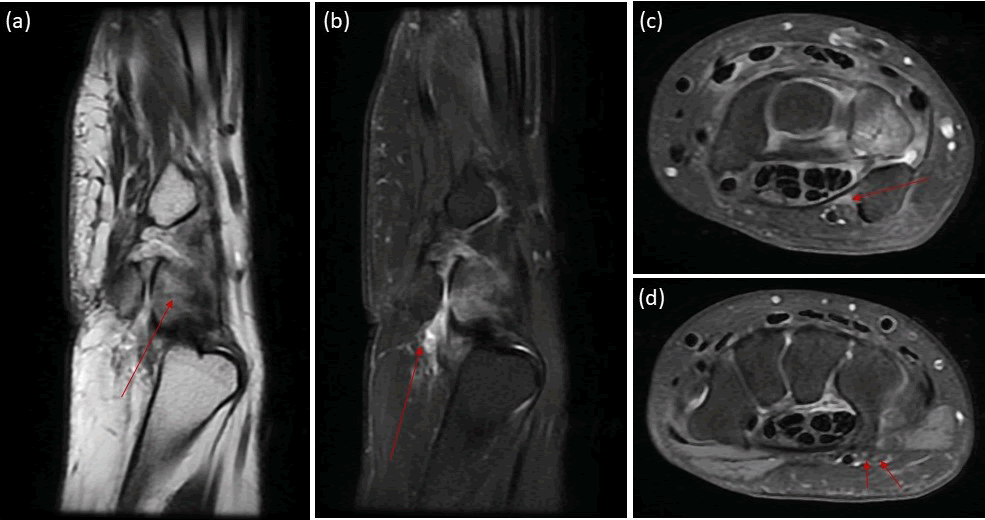

Wrist MRI revealed ruptured pisotriquetral joint ganglion cyst with surrounding free fluid extending to the proximal Guyon’s canal. The latter is compressing the proximal ulnar nerve (Zone I). There is bone marrow edema related to triquetrum with low signal intensity line suggesting fracture (Figure 2).

Figure 2. a) Wrist MRI, sagittal T1; b) sagittal PD fat saturation, c) axial PD fat saturation sequences at the level of proximal and d) distal Guyon’s canal. Triquetrum bone marrow edema with intramedullary low signal intensity line denoting fracture (arrow in (a)). Pisotriquetral ganglion cyst with surrounding free fluid and edematous changes denoting rupture (arrow in (b)). Free fluid noted in the proximal Guyon’s canal (zone I) causing mass effect on the ulnar nerve (arrow in (c)). The superficial and deep branches of the ulnar nerve demonstrate normal thickness and signal intensity (arrows in (d)).

While ganglion cysts and triquetrum fractures are established causes of ulnar nerve compression in Guyon’s canal, our case involves dual etiologies resulting from a traumatic event. Unlike typical Guyon’s canal syndrome, where the ganglion cyst is the primary cause, in our patient, ulnar nerve compression was due to free fluid that leaked from the cyst and extended into Guyon’s canal. Additionally, the triquetrum fracture compounded the trauma, leading to the patient’s symptoms.